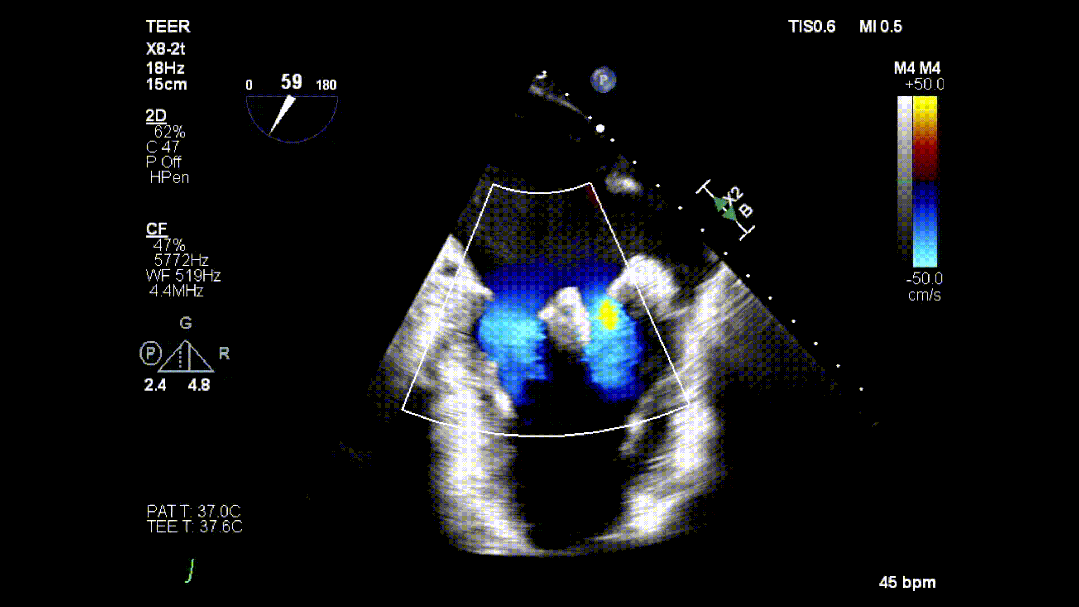

本次培训的“重头戏”—— 两台高难度 TEER 手术沉浸式观摩,将培训氛围推向高潮。手术病例分别为 “P2 宽大脱垂病变” 与 “早期 Barlow 病变”,由厦门大学心血管病医院团队与浙江大学附属邵逸夫医院团队协同完成。术中,专家团队操作精准、配合默契,不仅完美展现了 TEER 技术在复杂病例中的应用优势,更通过实时讲解,让学员直观掌握手术关键步骤、解剖评估要点与应急处理思路。

病例2: